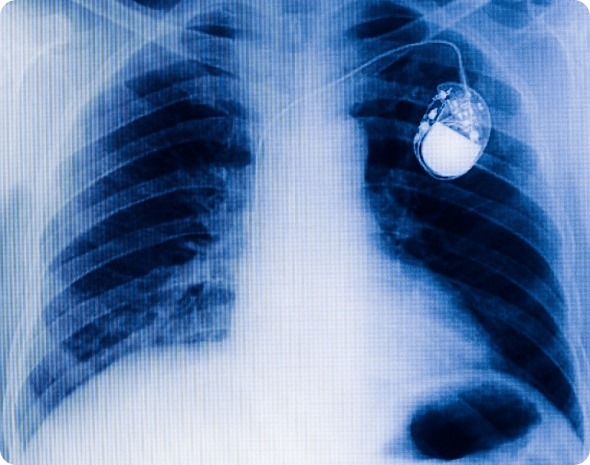

chest with the pacemaker on x-ray film

Traditional chest pacemaker one x-ray film.